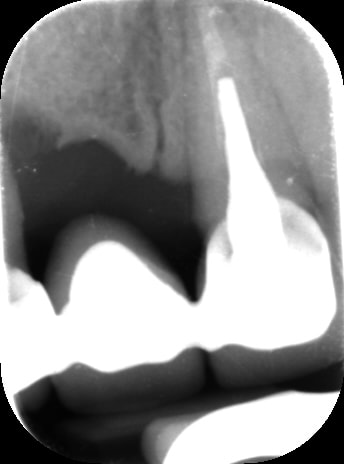

Bon voila le scann de 11-12 (pas 21-22 comme noté)

C'est vrai que j'ai à mort d'os en épaisseur.

Le manque est surtout en hauteur.

Dans tous les cas je refais 21 en même temps.

Tu ne ferais qu'un conjonctif enfoui ? Tu crois que c'est fiable dans le temps ?

j'ai l'impression qu'il ne manque pas d'os en verticale, ou à peine en 12.

Un bon cj avec un lambeau décalé en palatin ou en rouleau pour gagner en épaisseur me semblerai suffisant

le montage guide RX laisse supposer un manque d'un mm en 12 et ok en 11. Surcomble en cj pour en éliminer au cas où avant les empreintes